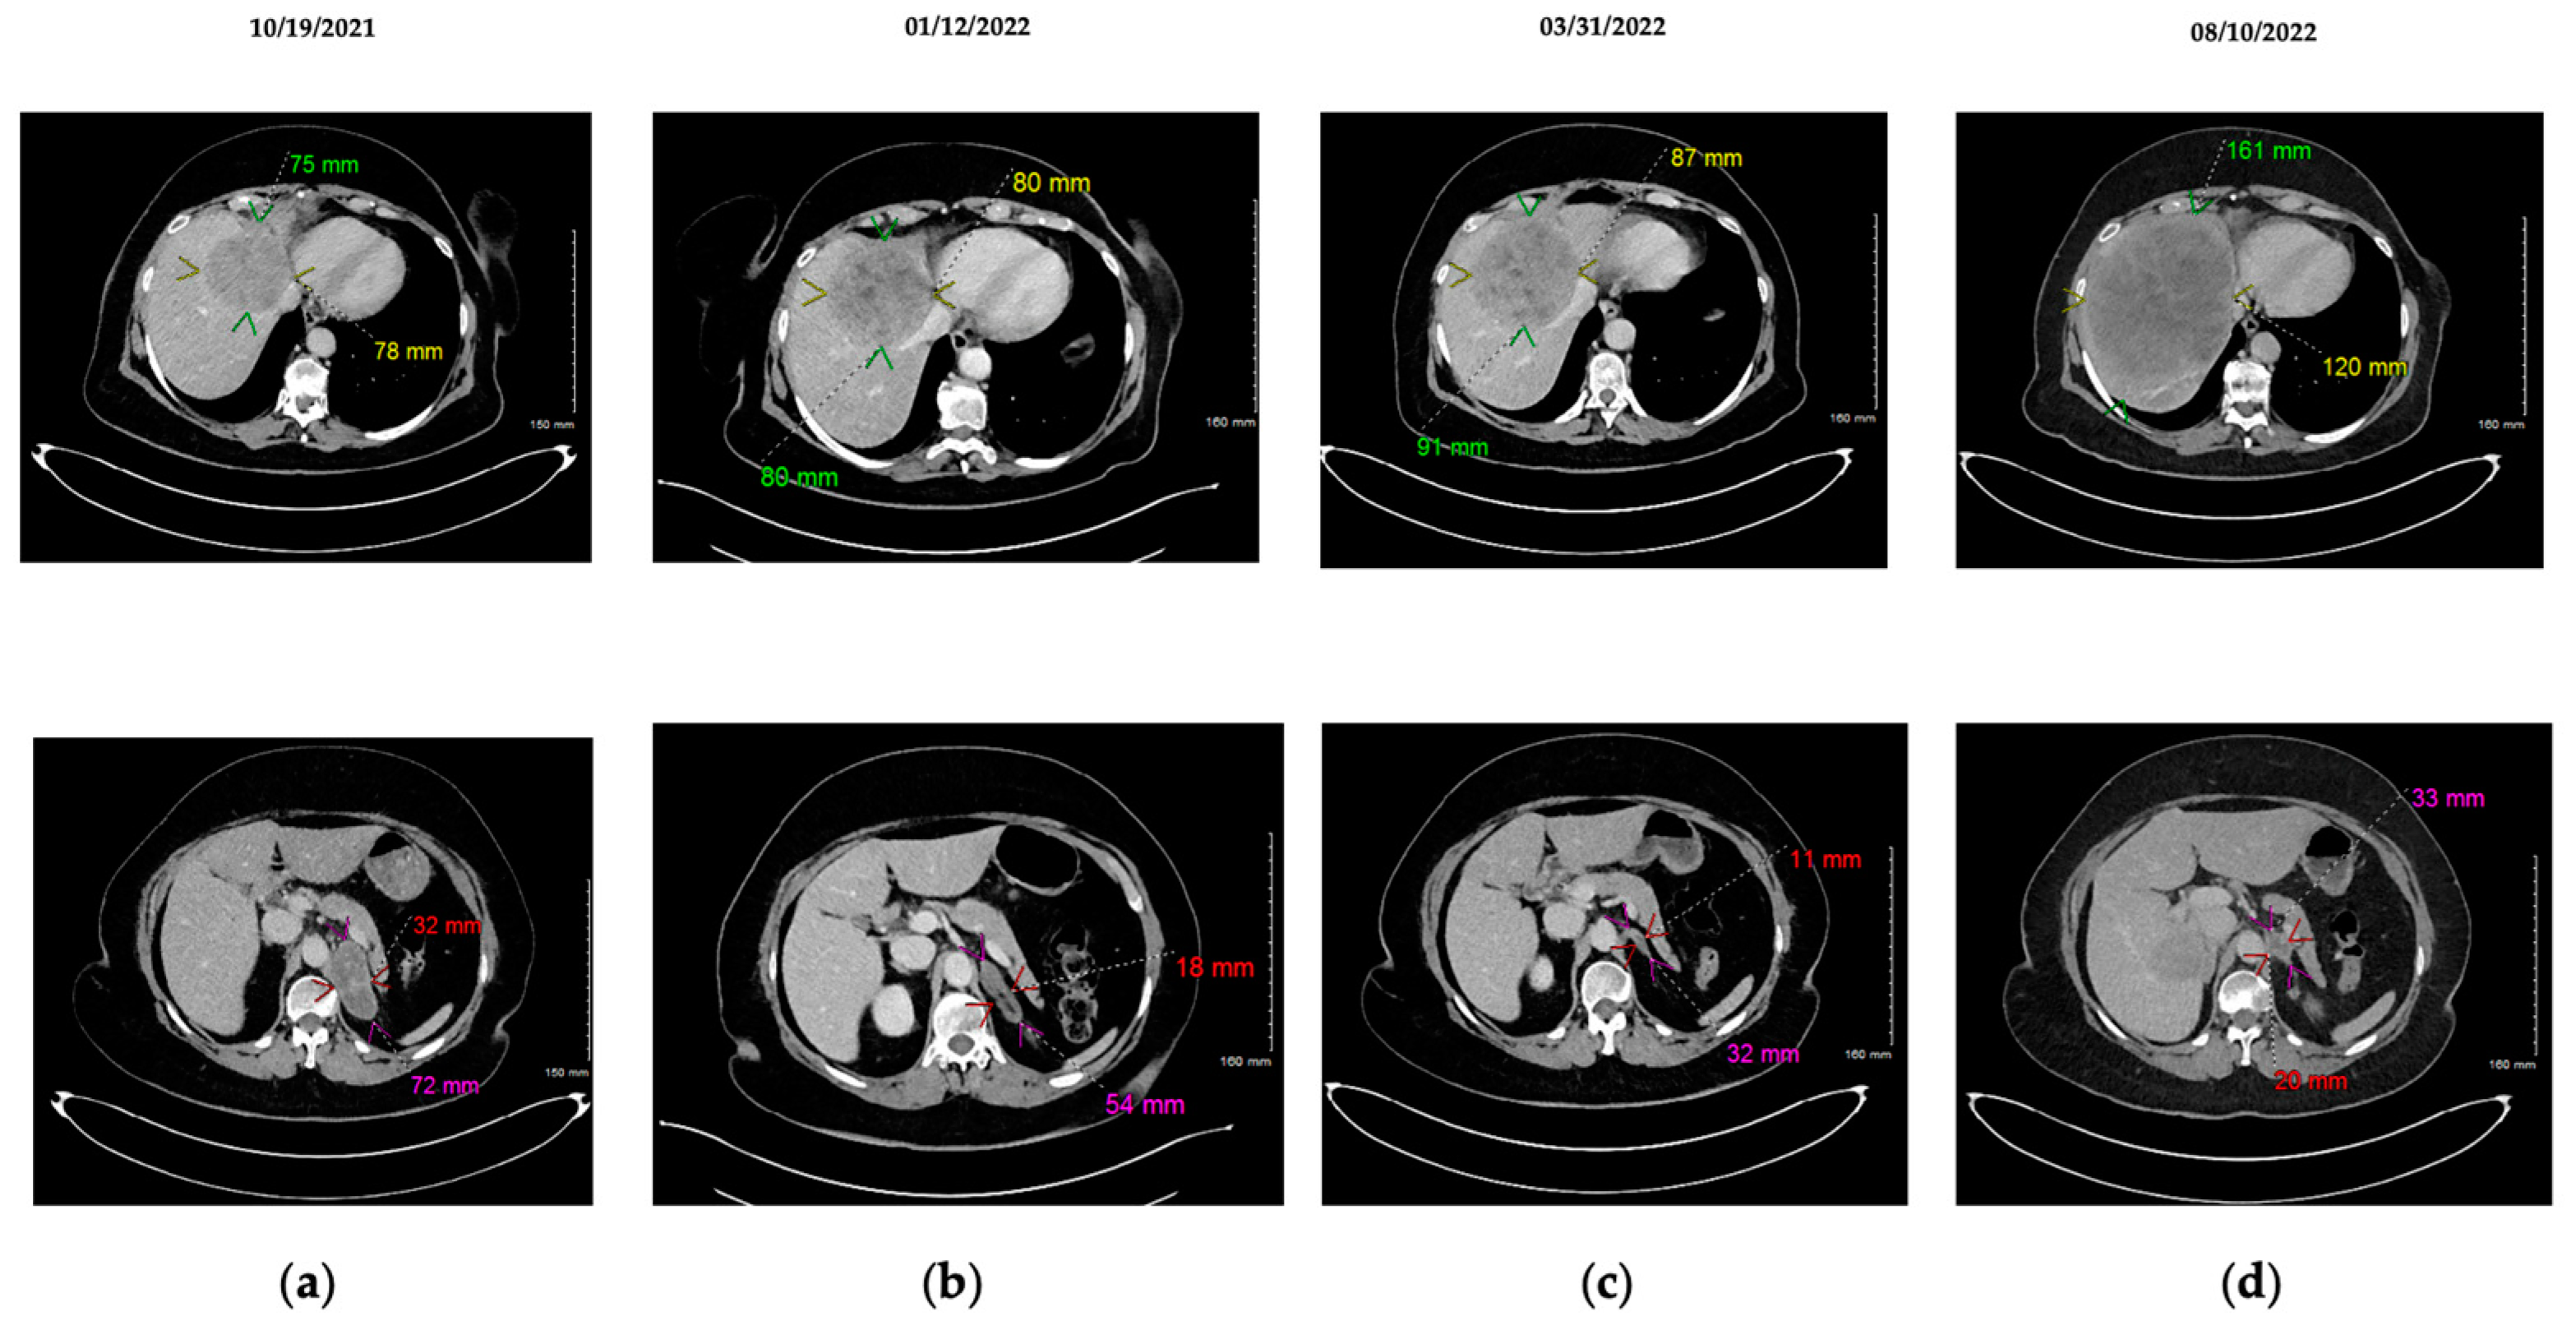

2.3. Appearance of MET Amplification as Resistance Mechanism to Osimertinib: Concomitant Administration of Imatinib + Osimertinib + Crizotinib